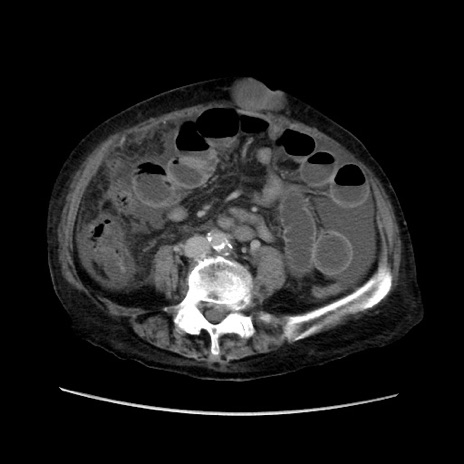

冠状断像

【症例】80歳代 女性

【主訴】腹部膨満感

【現病歴】他院にて肝硬変にてフォロー中。1週間前から便秘、腹部膨満感、臍部腫瘤あり受診となる。

【既往歴】肝硬変

【身体所見】腹部膨隆あり、皮膚変化なし、疼痛なし。

【データ】WBC 4600、CRP 0.25